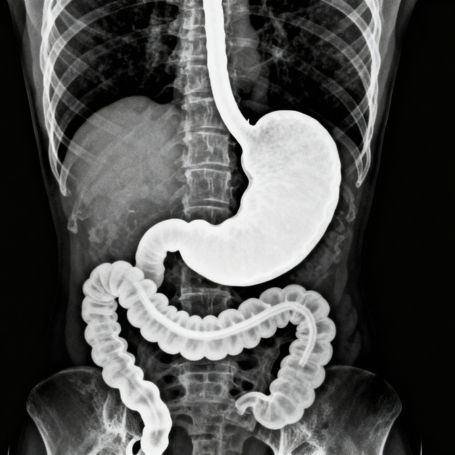

Barium Meal is a specialized diagnostic test that helps doctors evaluate the upper digestive tract, specifically the stomach and the first part of the small intestine, using advanced X-ray imaging. During the test, a patient swallows a chalky liquid containing barium sulfate. This contrast agent coats the lining of the stomach and duodenum, allowing detailed visualization of their structure on X-rays. This test is crucial for detecting abnormalities like ulcers, tumors, or blockages, providing valuable insights into digestive health.

The Barium Meal test plays an important role in diagnosing conditions affecting the stomach and upper small intestine. It helps identify structural issues like narrowing (strictures), ulcers, inflammation, and abnormal growths. It is often recommended when symptoms such as persistent abdominal pain, indigestion, or difficulty swallowing are present. The test also assists in evaluating reflux disease and guiding further treatment decisions.

Parameters Evaluated in Barium Meal

The parameters assessed during this test include:

1. Stomach shape and size

2. Mucosal lining (looking for ulcers or lesions)

3. Presence of any narrowing or obstruction

4. Stomach emptying and motility

5. Condition of the duodenum (first part of the small intestine)

This detailed assessment helps diagnose various gastrointestinal diseases effectively.